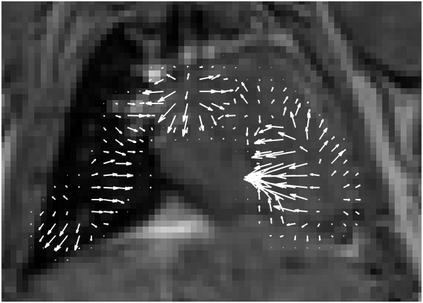

Various imaging modalities allow for time-dependent image reconstructions from measurements where its acquisition also has a time-dependent nature. Magnetic particle imaging (MPI) falls into this class of imaging modalities and it thus also provides a dynamic inverse problem. Without proper consideration of the dynamic behavior, motion artifacts in the reconstruction become an issue. More sophisticated methods need to be developed and applied to the reconstruction of the time-dependent sequences of images. In this context, we investigate the incorporation of motion priors in terms of certain flow-parameter-dependent PDEs in the reconstruction process of time-dependent 3D images in magnetic particle imaging. The present work comprises the method development for a general 3D+time setting for time-dependent linear forward operators, analytical investigation of necessary properties in the MPI forward operator, modeling aspects in dynamic MPI, and extensive numerical experiments on 3D+time imaging including simulated data as well as measurements from a rotation phantom and in-vivo data from a mouse.